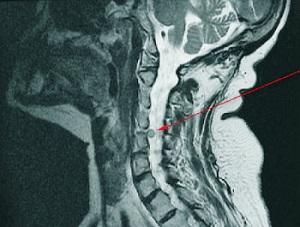

Для диагностики используются методы, такие как МРТ, УЗИ и рентгенография головы и шеи. Обратиться за консультацией можно как к терапевту, так и к врачу-отоларингологу.